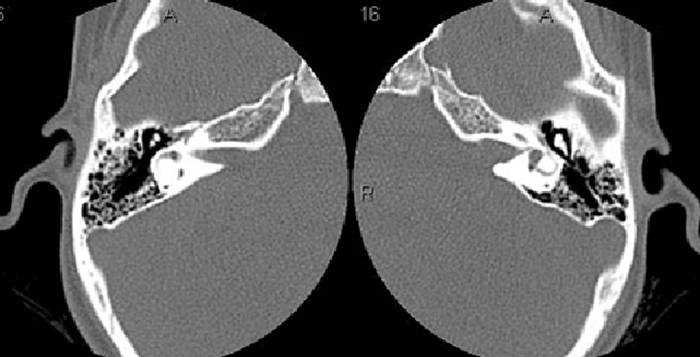

При развитии отклонений в этом отделе показана КТ среднего и внутреннего уха, которая причислена к безболезненным неинвазивным диагностическим приемам. Принцип действия компьютерного томографа заключается в ионизирующем излучении и его возможностях проходить сквозь ткани. Обследование рекомендовано при неудовлетворительных результатах других способов исследований, а также, когда требуется установить истинную причину заболевания ЛОР-органов и диагноз. С помощью сканирования получаются трехмерные изображения с минимальными срезами, на которых визуализируются самые незначительные патологии.

На многосрезовых снимках после компьютерного скрининга отображается:

- система каналов, которая отвечает за качество слуха;

- нервы лицевой области;

- яремная вена;

- сонная артерия;

- сосудистые стенки;

- барабанная кость и прочее.

Во время диагностического сканирования рентген-импульсы трансформируются в электросигналы, которые поддаются компьютерной обработке. В ходе этого создаются послойные изображения с визуализацией анатомии уха и его отклонениями. Готовые результаты расшифровываются рентгенологом. При постановке предварительного медицинского заключения лаборант уделяет внимание таким показателям:

- размерам внутреннего прохода;

- состоянию костного туннеля;

- присутствию воспалительных областей и опухолей.

В зависимости от изучаемого района, патологические отделы и новообразования отображаются на результатах темными и светлыми пятнами.